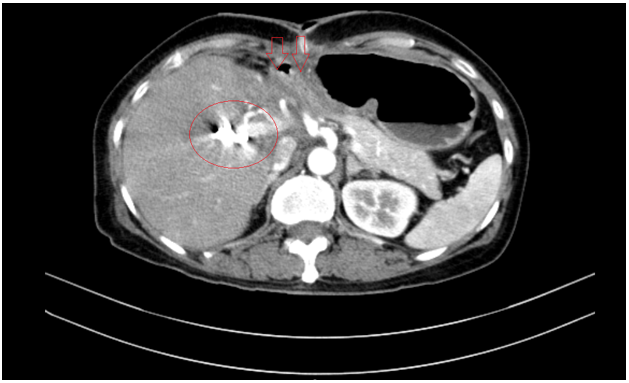

Chụp cắt lớp vi tính bụng - tiểu khung: Hình ảnh giãn đường mật trong gan phải/Sonde dẫn lưu đường mật gan phải - Gan trái đã cắt.

Hình 7. Phim chụp cắt lớp vi tính vụng cho thấy phần gan trái đã cắt (hình mũi tên)- Sonde dẫn lưu đường mật gan phải( vòng tròn đỏ).